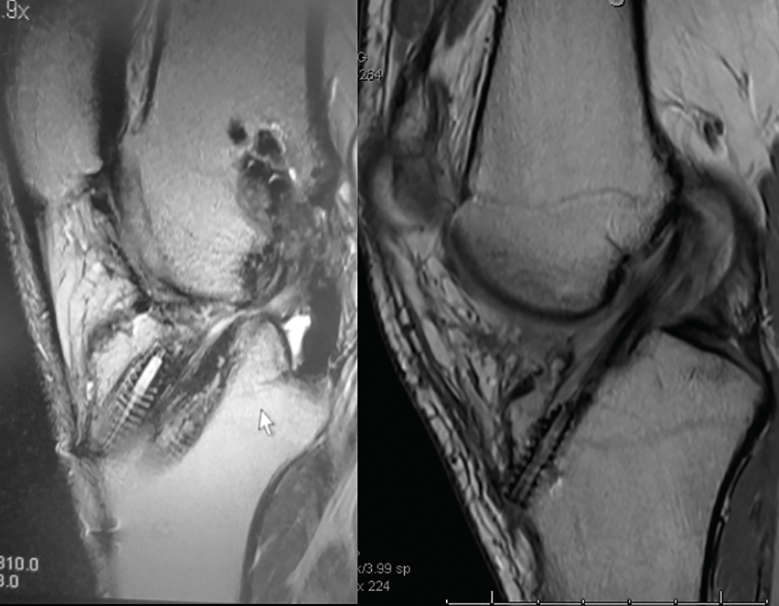

Figura 1. Imagen radiológica que permite identificar una técnica de reconstrucción transtibial o “monotúnel” (izquierda) respecto a una técnica anatómica (derecha).

El estudio radiológico recomendado debería incluir proyecciones anteroposteriores y laterales, axiales de rótula, telemétricas de la extremidad inferior y también en posición de Schuss (en carga y con unos 30° de flexión de la rodilla). La radiología simple va a permitir identificar qué técnica quirúrgica se realizó inicialmente y qué material se utilizó para la fijación (Figura 1). La proyección en Schuss permite observar si existen cambios degenerativos en los compartimentos femorotibial interno o externo de la rodilla de forma más precisa que con la radiología simple en decúbito supino. Finalmente, la radiografía telemétrica de las extremidades inferiores va a permitir conocer el eje mecánico de la extremidad. La existencia de deformidades en el plano coronal se ha asociado a un incremento de la solicitación mecánica del LCA y también del riesgo de rotura de la plastia (Figura 2)(21).